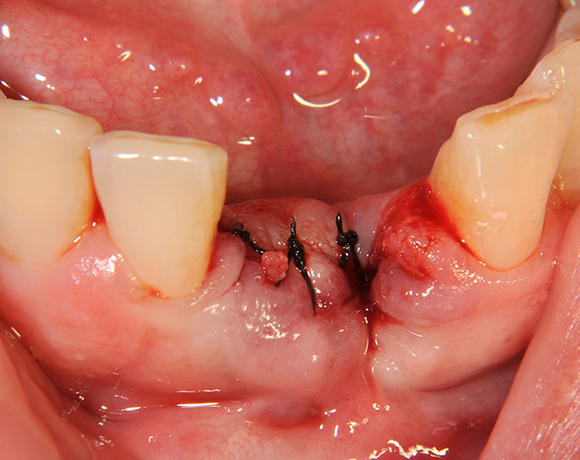

Die Keramikimplantate der Fa. Dentalpoint lassen sich auch zur Sofortimplantation verwenden. Das bedeutet, dass nach Extraktion nicht beherdeter Zähne direkt die Implantate gesetzt werden können.

Im vorliegenden Patientenfall wurden die beiden nicht erhaltungswürdigen, mittleren Unterkieferschneidezähne durch zwei Vollkeramikimlpantate ersetzt.